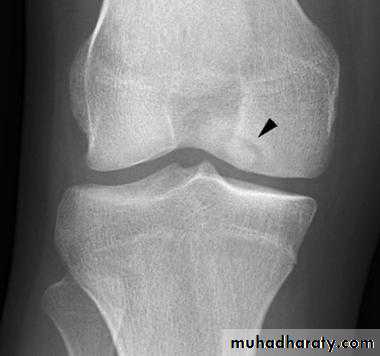

Osteochondritis dissecans of the medial femoral condyle

Osteochondritis dissecans of the medial part of the articularsurface

Osteochondritis dissecans :

affects the large articular surface , commomnly medial femural condylee ,talus and trochlea .

Ends by separation of the affected part in to the joint space resulting in intra-articular loose body .